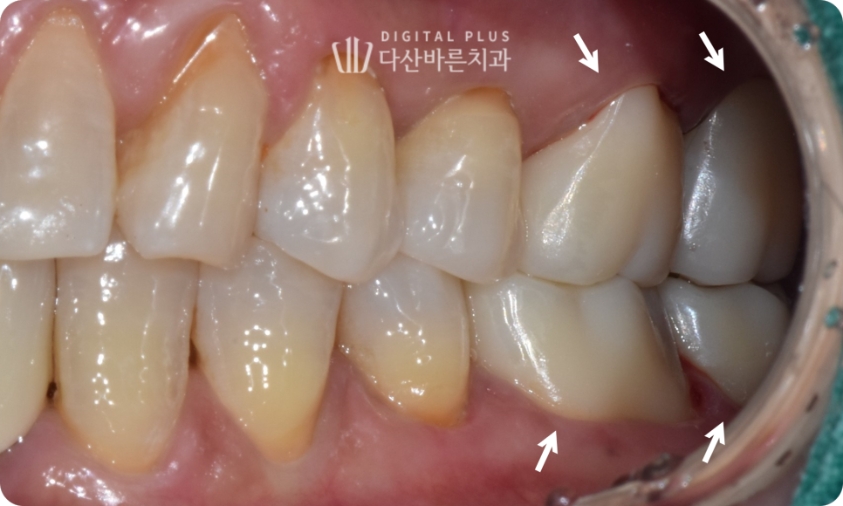

두 번째 환자분 케이스입니다. 해당 환자분은 좌측 아래 가장 끝 어금니가

빠진지 오래된 상태셨는데요. 이로 인해 마주하고 있는 위쪽 대합치가

아래쪽으로 정출된 상태가 확인됩니다.

▲ 초진 시 구강 사진. 왼쪽 아래 어금니를 빠진 채 방치하여 위 대합치가 정출된 상태.